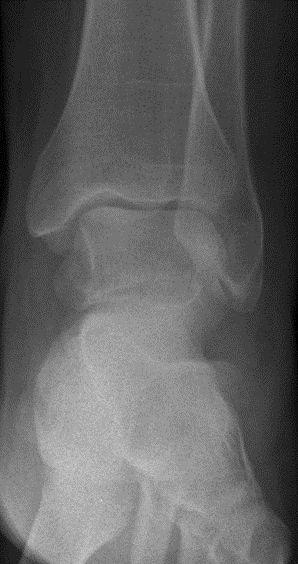

Die Röntgenuntersuchung ergab keinen pathologischen Befund. (Abb.1 und 2)

Abb.1 Unfallbild a.p.

Abb.2 Unfallbild seitlich

Der Bruch des Sprungbeines war auf den nach dem Unfall angefertigten Röntgenbildern nicht erkennbar und wurde erst bei der MRT/CT Untersuchung 9 bzw. 11 Wochen nach dem Unfallereignis festgestellt.